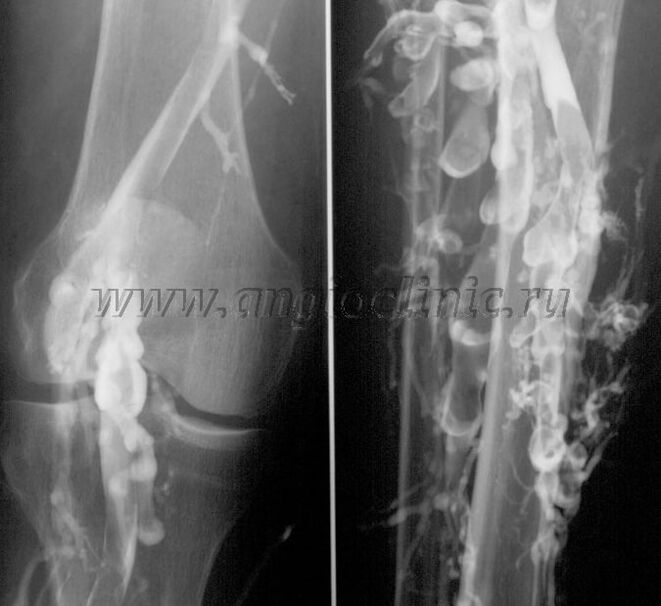

Kontraste benografia

Normalean, ultrasoinu eskaneatzea nahikoa da venous-patologiaren diagnostiko osoa egiteko, baina kasu batzuetan beharrezkoa da sakoneko eta azaleko venous-sistemaren egoeraren arteko erlazioa aztertzea, batez ere barizeak eta bigarren mailako barizeak errepikatzen direnean.

Arazo hauek konpontzeko, X izpien kontraste azterketa erabiltzen da. Saphenous benak zulatzen dira eta kontrastea ematen da. X izpien makinaren monitorean kontrastearen mugimendua ikusten da, eta beharrezko proba eta proiekzio guztiak egiten dira. Gaur egun, barizeentzako benografia oso gutxitan erabiltzen da.